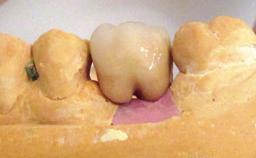

Biological complications caused by undetected cement residue have been receiving much attention. Excess cement might be responsible not only for rapidly developing of peri-implantitis, but also for delayed or chronic manifestations of the disease many years after cementation (Wilson 2009; Linkevicius and coworkers 2013). Invitro and clinical studies have shown that it is very difficult or even impossible to completely clean up excess cement at subgingival margins, so popular in cemented restorations (Agar and coworkers 1997; Linkevicius and coworkers 2011, 2012). Possible outcomes of biological complications due to excess cement range from temporary inflammation of the peri-implant soft tissues without any serious esthetic and functional consequences all the way to implant loss. This report describes a case of peri-implantitis caused by residual cement; as well as the management and quite unusual resolution of the complication. The patient presented in 2009 with a draining sinus tract, tenderness on chewing, and tissue contact above the implant-supported restoration. The implant had been restored approximately three years before.